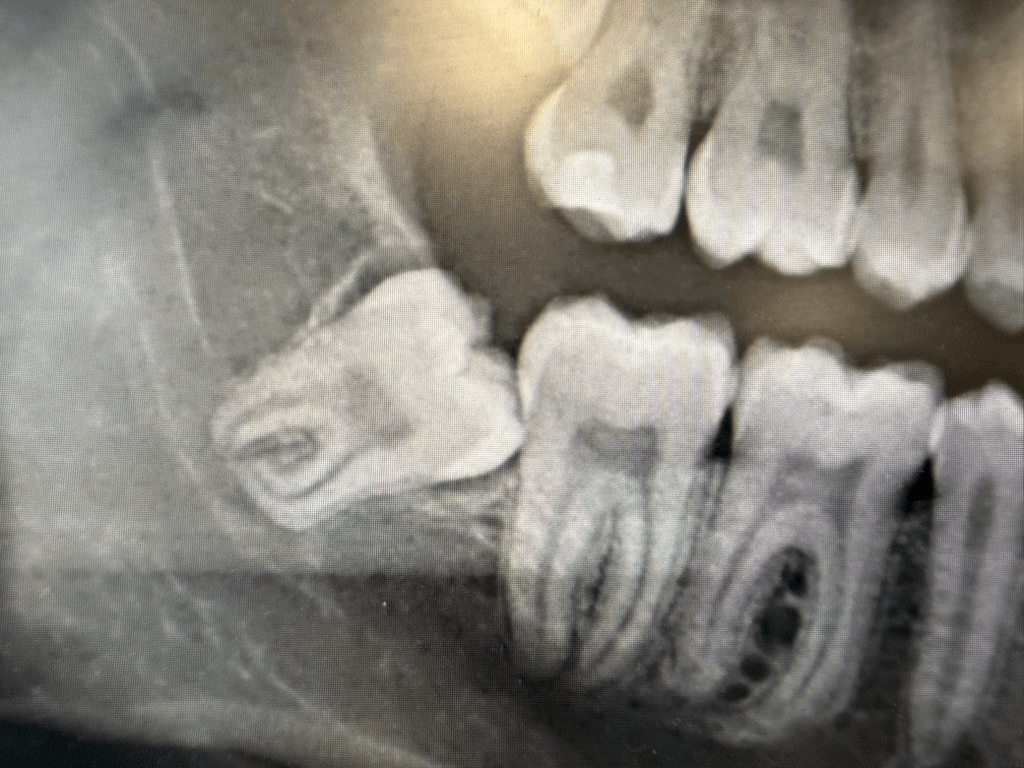

De fleste der får fjernet deres visdomstænder er ml. 18-20 år. Visdomstænder er ikke til nogen stor gavn, men er et levn fra fortiden. Med tiden er menneskets kæber blevet mindre, hvorfor der ofte ikke plads til visdomstænderne. Med manglende plads kan der opstå betændelse og smerter i kæbeleddet. En rapport fra 2001 har vist at ca. 80% af alle visdomstænder skal fjernes, og jo før jo bedre. Man heler markant bedre inden 25års alderen. Derudover anbefaler jeg at få dem fjernet inden roden er færdigdannet, så den ikke kommer i nærheden af nervus alveolaris inferior, som ligger i bunden af kæben.

En visdomstand er nr 8. Den skal fjernes hvis den kun er halvt frembrudt, eller hvis den ligger under tandkødet med retning imod 12 års tanden, som er tand nr 7 i rækken. Tilstanden er ofte ledsaget af dårlig ånde, dårlig smag, synkebesvær, hævelse, smerter og nedsat gabeevne. Det mest er alvorlige er dog at der kan opstå caries eller parodontose bag på tand nr 7, fordi der igennem længere tid har gemt sig bakterier, som du ikke slev kan børste væk. Dette forekommer ofte før eller siden, og det er meget mere forebyggende at få dem fjernet som ung end som ældre, da komplikationerne efter en visdomstandoperation vokser med alderen.

En visdomstand skal fjernes, hvis den ikke er helt frembrudt, og der gentagende gange har været betændelse omkring tandkødet. Den kan også asymptomatisk, men ligge så skævt at den medfører bakterier bag tand nr 7. Dette kan give caries, parodontose eller resorbtioner bag på tand nr 7. Dette kan være så alvorlig t for tand nr. 7 at den skal fjernes. Derfor er det meget forebyggende at få fjernet tand nr 8, så tand nr 7 altid kan holdes ren og intakt. Hvis der er betændelse omkring visdomstanden kan det medføre dårlig ånde, dårlig smag, synkebesvær, hævelse, smerter og nedsat gabeevne.